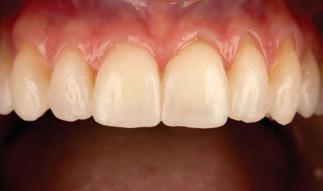

Fig. 2a: Patient was concerned about the discoloration on the two upper central incisors.

Fig. 2b: Old restorations were removed, and the surface was air-abraded with 50-micron aluminum oxide.

Fig. 2c: Freehand technique used to close the diastema.

Fig. 2d: The final result is at the one-year recall.